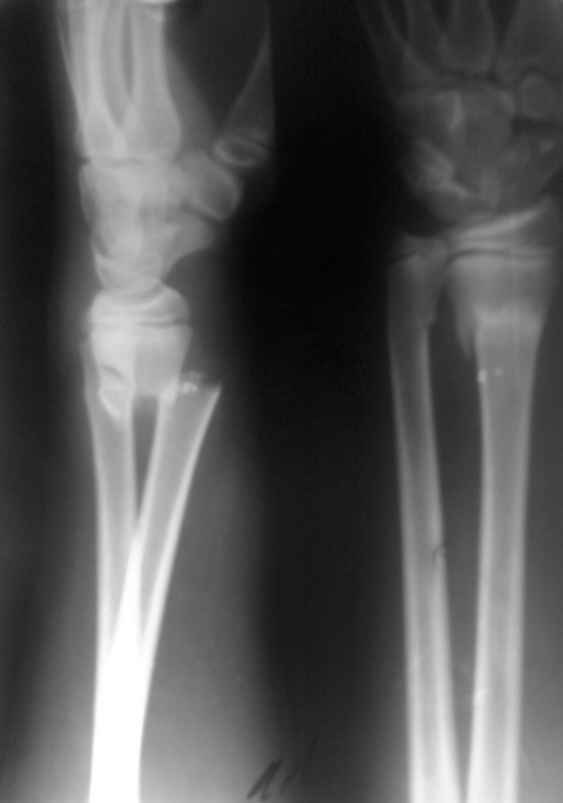

больной 13 лет.

травма полтора месяца тому.

Был сделан рентген, после чего закрытая репозиция под общим наркозом и наложена гипсовая повязка до средней 3 плеча.

пришли теперь спустя полтора месяца. На контроле, сделанном сегодня - такая ситуация.

ртг сделано без гипса. визуальных деформаций не видно. Припухлости нету. Жалоб малейших нету.

Что вы скажете про данный случай. Рентгенологически мне это очень не нравится.